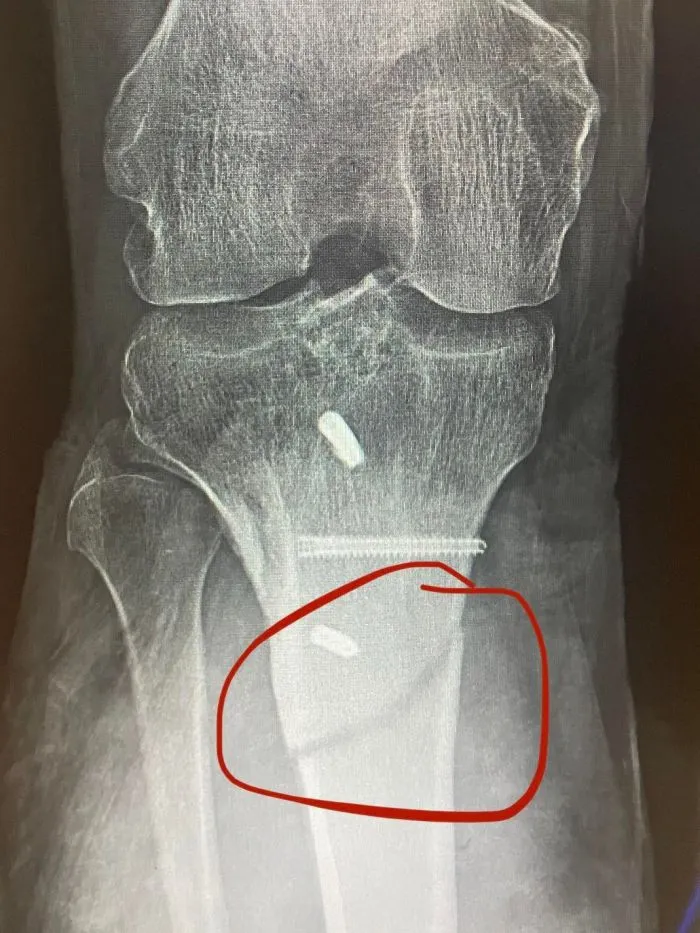

1. "Отправился на обычную 5-километровую пробежку. Посреди пробежки моя нога хрустнула.."